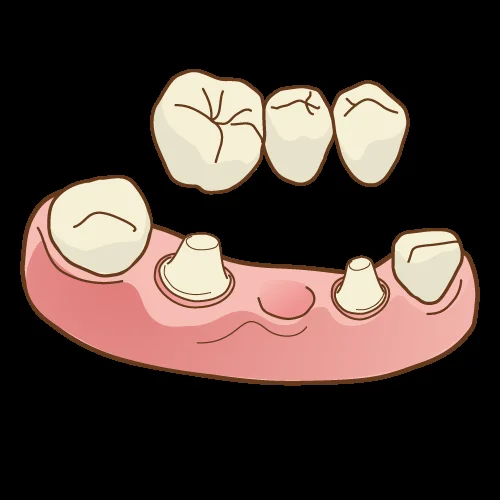

さて、今日は「ブリッジ」についてです。

そもそもブリッジとはどういう治療方法かというと・・・

歯周病や虫歯によって歯が無くなってしまった所の両隣の歯を大きく削って、繋ぐ治療法です。

歯の無い部分を川に見立てて、橋を架けるように行うので、ブリッジと言われます。

そして、通常、ブリッジを行う場合には前後の歯を「クラウン」の形で大きく削る必要があります。

ただし、ブリッジとは前後の歯とも全周を削るクラウンと言われる形態で作られるのが教科書的に正しいと言われているやり方です。

その対策として使用されるのが、クラウン形態のブリッジではなく、インレー形態のブリッジです。

インレー形態のみで作成するブリッジの事をインレーブリッジと言います。

こういう感じですね。